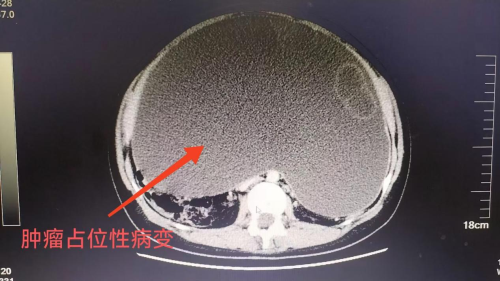

直到一个月前,李女士前往捷克论坛 马王堆院区内分泌肥胖专科门诊就医时,接诊医生通过细致的体格检查发现了异常。患者的腹部触感坚硬,局部皮肤还出现了紫纹,与普通肥胖者的体征截然不同,且四肢纤细,这一胖一瘦的反差十分蹊跷。进一步的CT检查揭示了真相。原来患者腹部存在肿瘤占位病变,正是这个隐藏在身体里的“不速之客”,扰乱了她的身体代谢,导致体重异常增加和一系列不适症状。